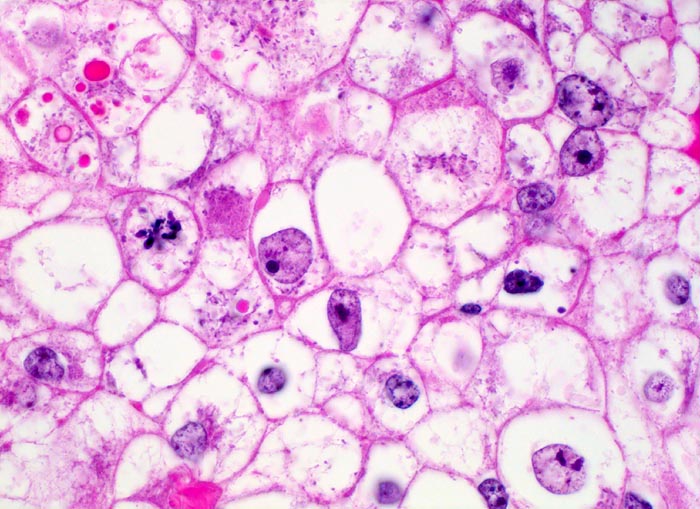

mässig differenziertes hellzelliges Nierenzellkarzinom

Klarzelliger Tumor mit deutlichen Zellgrenzen. Das reichlich vorhandene Zytoplasma ist entweder klar oder fein granuliert. Ein Teil der Tumorzellen enthält rote intrazytoplasmatische hyaline Globuli. Mitose.

Hyaline Globuli können oft bei Nierenzellkarzinomen beobachtet werden. Sie kommen aber auch in vielen anderen Tumoren (Bsp. Hepatozelluläres Karzinom, Dottersacktumor) und in gutartigen Veränderungen vor. Die genaue Ätiologie und Bedeutung der Einschlüsse ist nicht geklärt.